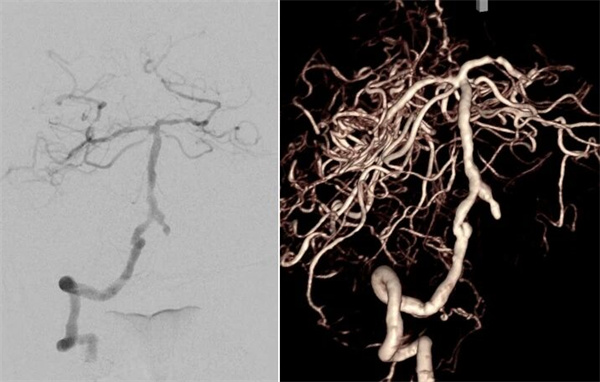

患者高先生,70岁,患有高血压病多年。2年前曾行冠状动脉搭桥术,平素规律服药。2个月前,他因左上肢突然麻木被送至清华大学垂杨柳医院急诊科就诊。头颅CT提示右侧顶叶少量蛛网膜下腔出血。后入住神经外科进一步诊治,全脑血管造影(DSA)结果显示:右侧椎动脉起始部重度狭窄约70%,左侧椎动脉颅内段闭塞;右侧椎动脉颅内段存在大小约3.5×2毫米的夹层动脉瘤;右侧颈内动脉颅外段存在重度狭窄,左侧颈内动脉通过前交通动脉代偿。

▲右侧椎动脉V4段夹层动脉瘤

▲右侧颈内动脉颅外段重度狭窄,左侧颈内动脉代偿右侧颅内